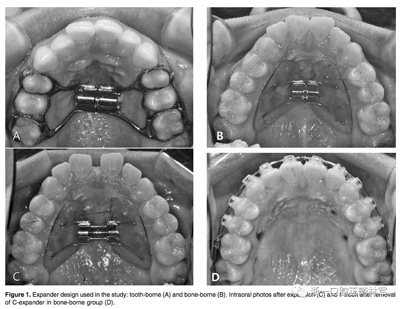

牙支持式快擴(kuò)的帶環(huán)設(shè)在第一前磨牙和第一磨牙上,見Figure 1A。骨支持式快擴(kuò)見Figure 1B-D,由直徑1.8毫米,長8.5毫米的四個(gè)微種植釘支撐,兩個(gè)位于尖牙與第一前磨牙之間,另外兩個(gè)位于第二前磨牙與第一磨牙之間的腭部牙槽骨中。 每天轉(zhuǎn)動(dòng)1/4圈(0.25毫米)。